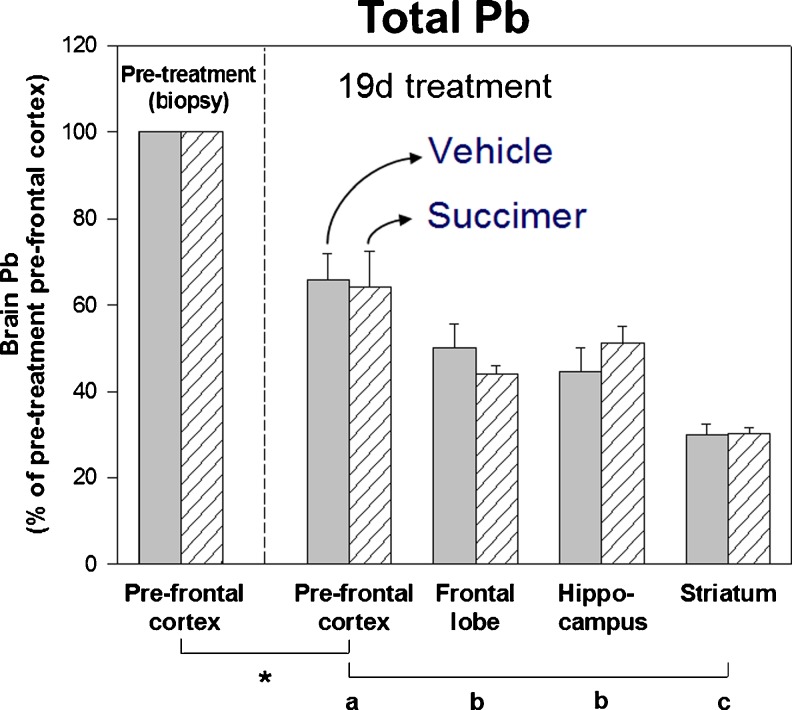

To best evaluate the extent that succimer treatment reduced brain lead levels, we normalized lead levels in various brain regions within each animal to the brain lead levels in each animal’s prefrontal cortex biopsy collected prior to starting succimer treatment. These data clearly show that there is no measurable reduction in brain lead levels as a result of the 19-day succimer treatment regimen, compared to the vehicle treatment (Fig. 10). Notably, there was a significant reduction in brain lead levels in all animals over the 19-day treatment period, as shown in the comparison of prefrontal cortex lead levels in the pre-treatment biopsy versus the post-treatment sample. There were also significant differences in lead levels across brain regions, consistent with results from prior studies. However, there were no differences in lead levels between the vehicle- and the placebo-treated groups, indicating that 19 days of succimer treatment was no more efficacious at reducing brain lead levels than the cessation of lead exposure alone.

Fig. 10.

Lead levels in brain prefrontal cortex (PFC, pre- and post-treatment), frontal lobe, hippocampus, and striatum of the vehicle- (solid bars, n = 5) and succimer- (hatched bars, n = 6) treated groups (lead levels expressed as a percentage of the pretreatment PFC level within each animal). Values are means (±SE). Mean values of lead concentrations in the pretreatment PFC biopsy for the vehicle- and succimer-treated groups were 1,980 and 1,410 ng/g dry wt., respectively. Symbols below the x-axis indicate: * = pre- and post-treatment mean values were significantly different; a, b, and c comparisons of post-treatment brain regions. Means with different letters were significantly different from one another. Data from Cremin et al. [13]. [Reprinted from Toxicology and Applied Pharmacology with permission from Elsevier]

Notably, results from the 204Pb tracer component of the study, which more specifically reflect elimination of lead exposure given a day or two prior to starting chelation treatment, show the same outcome as total lead levels. That is, there were significant reductions in brain 204Pb levels over the19-day treatment period, as well as significant differences in brain 204Pb levels across brain regions (Fig. 11). But, there was no difference between the vehicle- and succimer-treated groups in brain 204Pb levels across any brain region. One noteworthy caveat to this interpretation is shown in the post-treatment prefrontal cortex brain region data from the vehicle and succimer groups blocked out in red in Fig. 11; those data suggest there was an increase in 204Pb tracer in the prefrontal cortex of the vehicle group over the 19-day treatment period, which most likely reflects the continued uptake (i.e., enrichment) of the 204Pb tracer into this brain region of the vehicle-treated animals over that period.